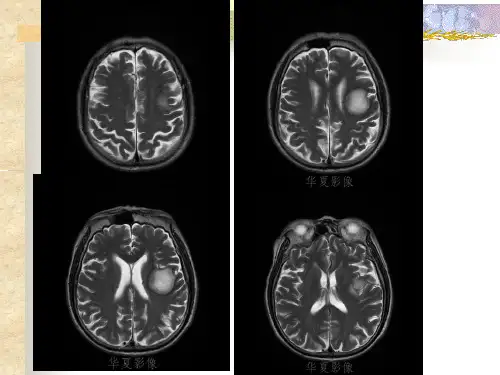

肿瘤样脱髓鞘病变影像特征以及鉴别诊断ppt课件